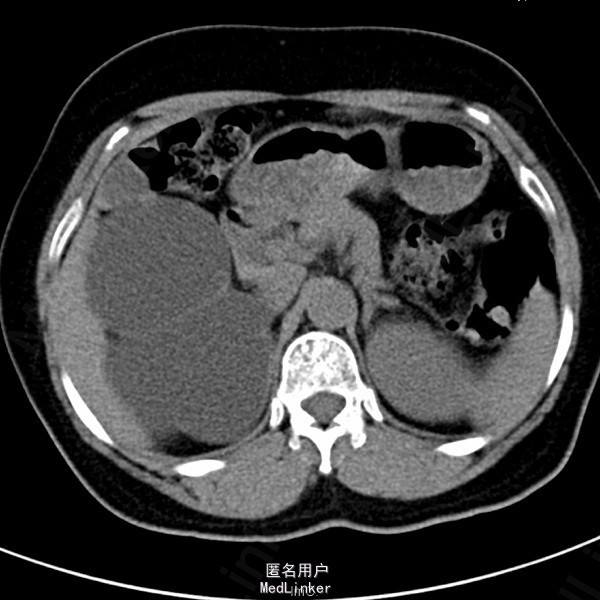

患者女,62岁11月,因“体检发现右肾积水4天”入院。自诉无任何不适。

超声检查示:1.右肾重度积水 2.右肾结石,疑右侧输尿管起始端结石 SPECT肾显像示:右肾无功能;左肾GFR代偿性增高,左上尿路引流通畅。

诊断:右输尿管上段结石 右肾重度积水无功能。行腹腔镜右肾切除术。术中见患者右肾实质菲薄,体积较大,与周围组织粘连重,穿刺吸出淡黄色尿液约1200ml。